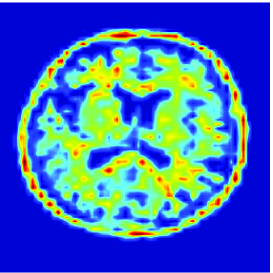

The proposed quadratic extension is illustrated in Fig. 4 where a graphical comparison with the Anscombe approximation is performed.

Here, is a uniform blur with . A () medical image shown in Fig. 5(a) is degraded by and corrupted by a Poisson noise following the model described in the previous section for various intensity levels. The degraded image is displayed in Fig. 5(b) when .

To evaluate the performance of our algorithm we use the Signal to Noise Ratio defined in Section 5.3.2. Tab. 2 shows the values of the obtained for different values of and . As predicted by Proposition 5.4(v), beyond some value of , which is dependent of , the optimal value is found. We also compare our results with those provided by two different approaches. The first one is the regularized Expectation Maximization (EM) approach (also sometimes called SMART) [10, 31] where the Poisson anti-likelihood penalized by a term proportional to the Kullback-Leibler divergence between the desired solution and a reference image is minimized. Its weighting factor has been adjusted manually so as to maximize the and, the reference image is a constant image whose pixel values has been set to the mean value of the degraded image. The other approach is the method based on the Anscombe transform proposed in [24] and discussed in Remark 5.6. For fair comparisons, the method here employs the same orthonormal wavelet representation, the same functions as ours and the same constraint set . It can be observed that the approach we propose gives good results. However, for high intensity levels (), the method based on the Anscombe transform performs equally well in terms of SNR. The restored images are shown in Fig. 5, when and after 3000 iterations. In spite of an important degradation of the original image, it can be seen that our approach is able to recover the main features in the image. It can also be noticed that the image restored by the two methods exhibit different visual characteristics.